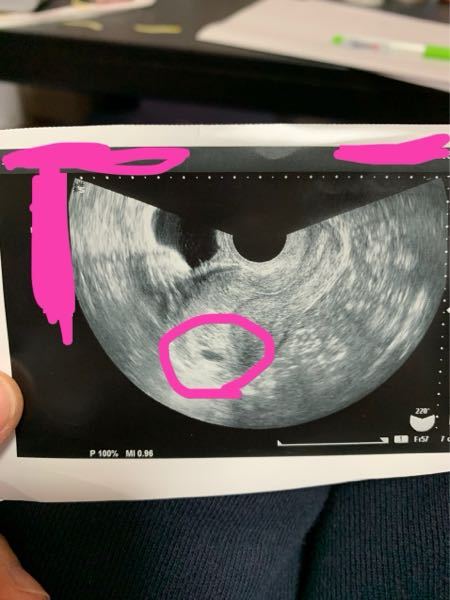

エコー写真について 5週ピッタリくらいに病院に行き 赤ちゃんはまだ見 Yahoo 知恵袋